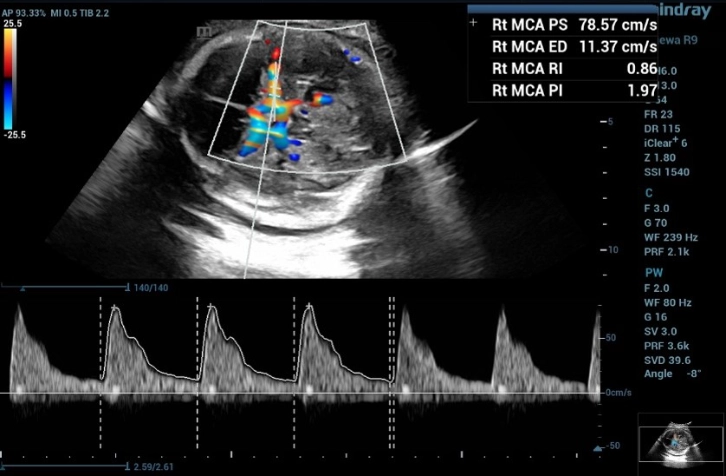

2. Middle Cerebral Artery Doppler for fetal anemia (Hb Bart's disease)

Fetal middle cerebral arterial (MCA) Doppler assessment is an important part of assessing fetal cardiovascular distress, fetal anemia or fetal hypoxia. In the appropriate situation it is a very useful adjunct to umbilical artery doppler assessment.

From the three MCA-PSV measurements in this fetus,

3rd MCA-PSV= 78.57 = 2.084 MoM (Figure 6)

MCA-PSV values ​​were greater than 1.55 MoM https://perinatology.com/calculators/MCA.htm

the third measurement of the doppler waveform of MCA in fetus with and the MCA-PSV value was 78.57 cm/s, which is greater than 1.55 MoM

Figure 6 Shows the third measurement of the doppler waveform of MCA in fetus with and the MCA-PSV value was 78.57 cm/s, which is greater than 1.55 MoM